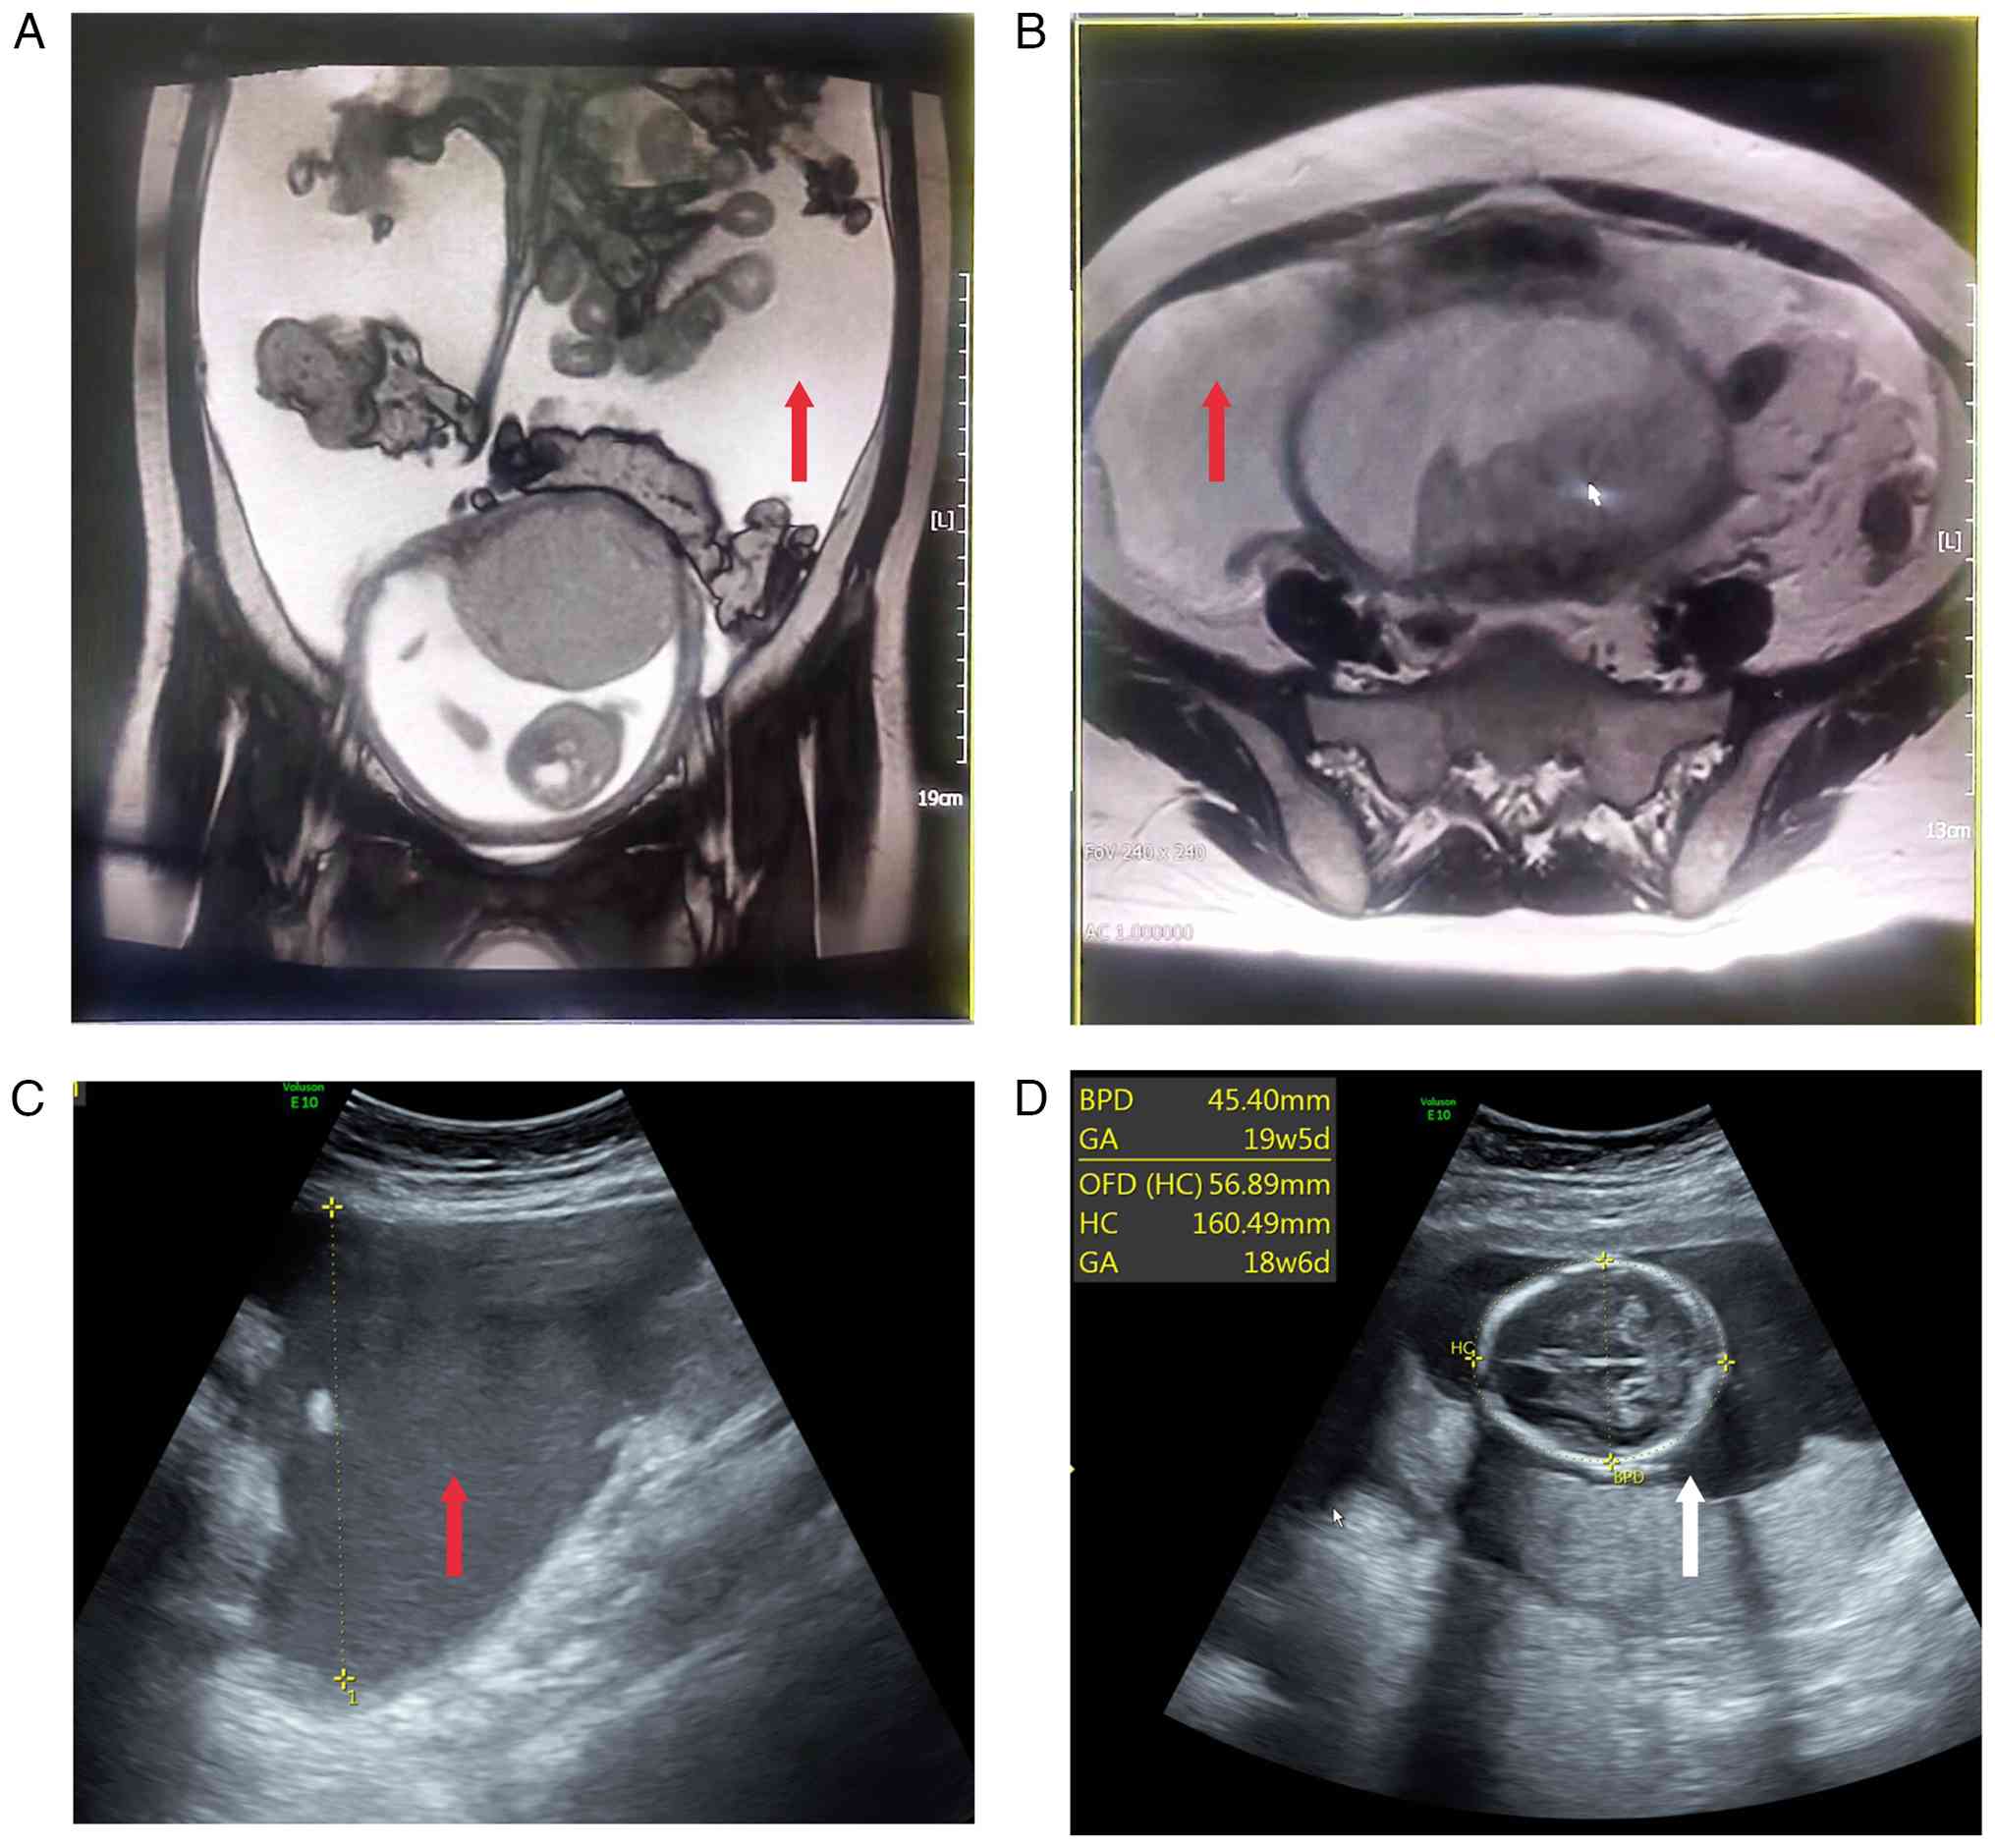

After abdominal paracentesis and tube placement, the patient experienced an improvement in symptoms, and the aspirated ascitic fluid was sent for further analysis. Supportive therapies, including intravenous nutrition, fluid replenishment and ketone reduction, were also initiated. During ultrasound-guided paracentesis, a gastric mass was noted, raising suspicion for gastric cancer. Yellow ascitic fluid was drained. Subsequent abdominal CT with contrast enhancement revealed a mass at the greater curvature of the gastro-pyloric junction, highly suspicious for malignancy, with alterations in the peritoneum and omentum, suggesting metastatic seeding (Fig. 2A and B).

Abdominal computed tomography,

endoscopy, cytology and histology of gastric signet-ring cell

carcinoma. (A) Coronal view and (B) transverse section of abdominal

CT, with the tumor indicated by the white arrow. (C) Endoscopic

view of the gastric lesion, with the tumor indicated by the white

arrow. (D) Cytological smear of ascitic fluid (magnification,

×400). (E) Microscopic examination of the biopsy (magnification,

×100). (F) Microscopic examination of the biopsy, revealing gastric

primary malignant cells with the signet ring cell indicated by the

red arrow (magnification, ×400).

Figure 2.

Abdominal computed tomography, endoscopy, cytology and histology of gastric signet-ring cell carcinoma. (A) Coronal view and (B) transverse section of abdominal CT, with the tumor indicated by the white arrow. (C) Endoscopic view of the gastric lesion, with the tumor indicated by the white arrow. (D) Cytological smear of ascitic fluid (magnification, ×400). (E) Microscopic examination of the biopsy (magnification, ×100). (F) Microscopic examination of the biopsy, revealing gastric primary malignant cells with the signet ring cell indicated by the red arrow (magnification, ×400).

The patient was informed of the findings, and an esophagogastroduodenoscopy was performed. The examination revealed a 5×4 cm raised mass near the greater curvature of the lower gastric body, adjacent to the gastro-pyloric junction, with two ulcers in the center, surrounded by irregular, nodular mucosa (Fig. 2C). Biopsy samples were taken from the ulcer edges for pathological examination, with gastric cancer highly suspected. Biopsy and ascitic fluid samples were fixed in 10% neutral-buffered formalin at room temperature for 12–24 h. Paraffin-embedded sections were cut at 4 µm. Routine H&E staining was performed at RT (hematoxylin 5 min, eosin 2 min). Cytospin smears of ascitic fluid were prepared by centrifugation at 1,500 × g for 10 min at room temperature, then fixed in 95% ethanol for 10 min and stained with H&E under the same as aforementioned. All slides were examined with an Olympus BX43 light microscope.

Pathological results from the gastroscopic biopsy indicated poorly differentiated gastric carcinoma, partially composed of signet ring cell carcinoma, classified as Lauren's mixed type. Concurrently, ascitic fluid cytology revealed proliferated mesothelial cells, small lymphocytes, macrophages and scattered atypical cells with irregular nuclei and mitotic figures, suggesting a possible tumor origin (Fig. 2D-F).